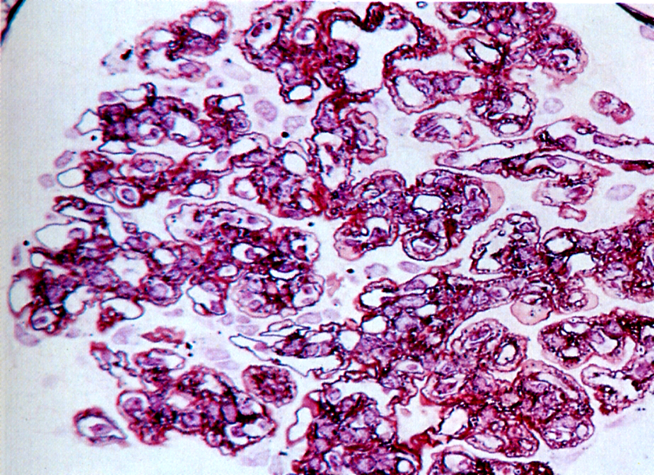

(1) 病理变化

大体:两侧肾脏对称性固缩,表面呈微小颗粒状,故称之为颗粒性固缩肾(granular nephrosclerosis)。切面观,皮质变薄,皮髓质分界不清。

光镜下:大量肾小球硬化、玻璃样变(超过全部肾小球的50%)。肾小球中央部分变为无细胞、嗜伊红、PAS阳性之玻璃样小体,周围部分纤维化(如下图)。少数肾小球结构残存。硬化肾小球所属肾小管萎缩、消失、使玻璃样变的肾小球相互靠拢集中。残留肾单位常呈代偿性肥大,肾小球体积增大,肾小管扩张。间质纤维组织增生并有大量淋巴细胞、浆细胞浸润。间质内小动脉硬化,管壁增厚,管腔狭窄。

(肾小球纤维化及玻璃样变,所属肾小管萎缩、消失。间质纤维化伴炎细胞浸润。)

(纤维被染成了蓝色)